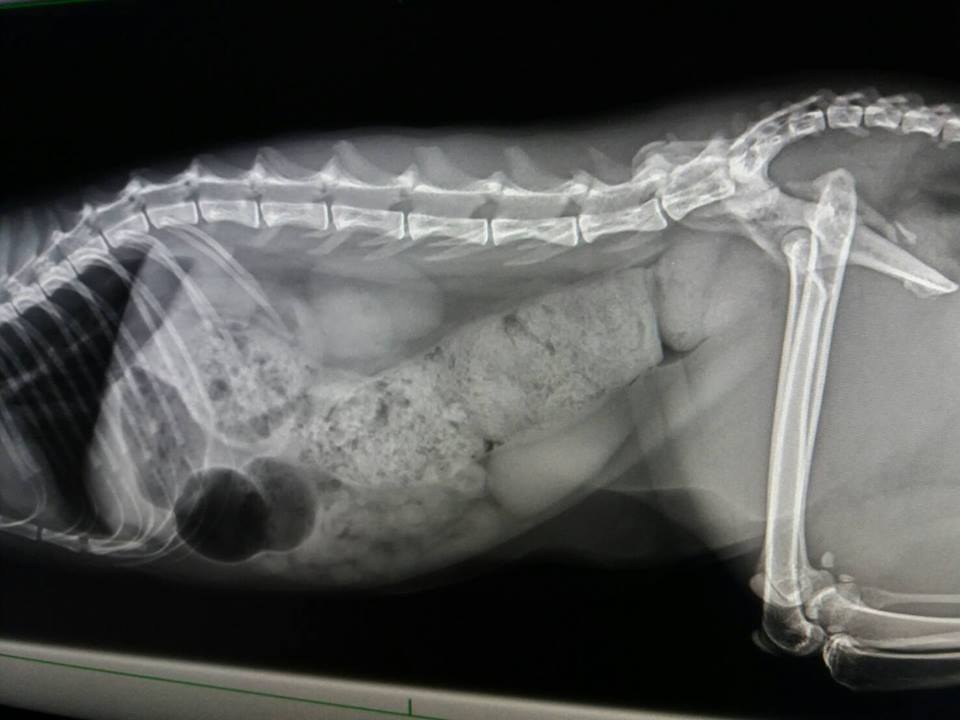

X光下發現大腸寬度變大,

認為有一可能導致艾咪雖有大便但無便意,等到積很久後,

後面大便已乾,